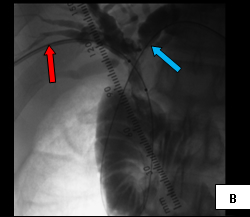

The first case (images A, B, and C), was an elderly man who came to me from a nursing home with advanced carcinoma of his common bile duct that severely narrowed the duct. The string of contrast outlining the very narrow common bile duct (red arrows, image A) and the dilated ducts above the narrowing (green and blue arrows, image A) testify to the severity of the disease. His left hepatic duct (blue arrow, image A) had been percutaneously decompressed elsewhere with a drainage catheter (yellow arrow, image A), but he remained jaundiced and ill.

So, coming through a fresh percutaneous access on his right side (red arrow, image B) and through the drainage catheter already in his left hepatic duct (blue arrow, image B), I concurrently deployed stents across the obstructed confluence of the hepatic ducts and across the common bile duct. The effect of the treatment is evident by comparing images A and C: decompression of the dilated right and left hepatic ducts, relief of the critical obstruction of the common bile duct, and quick movement of copious amounts of the injected dye (which correlated with the movement of bile) into the duodenum.